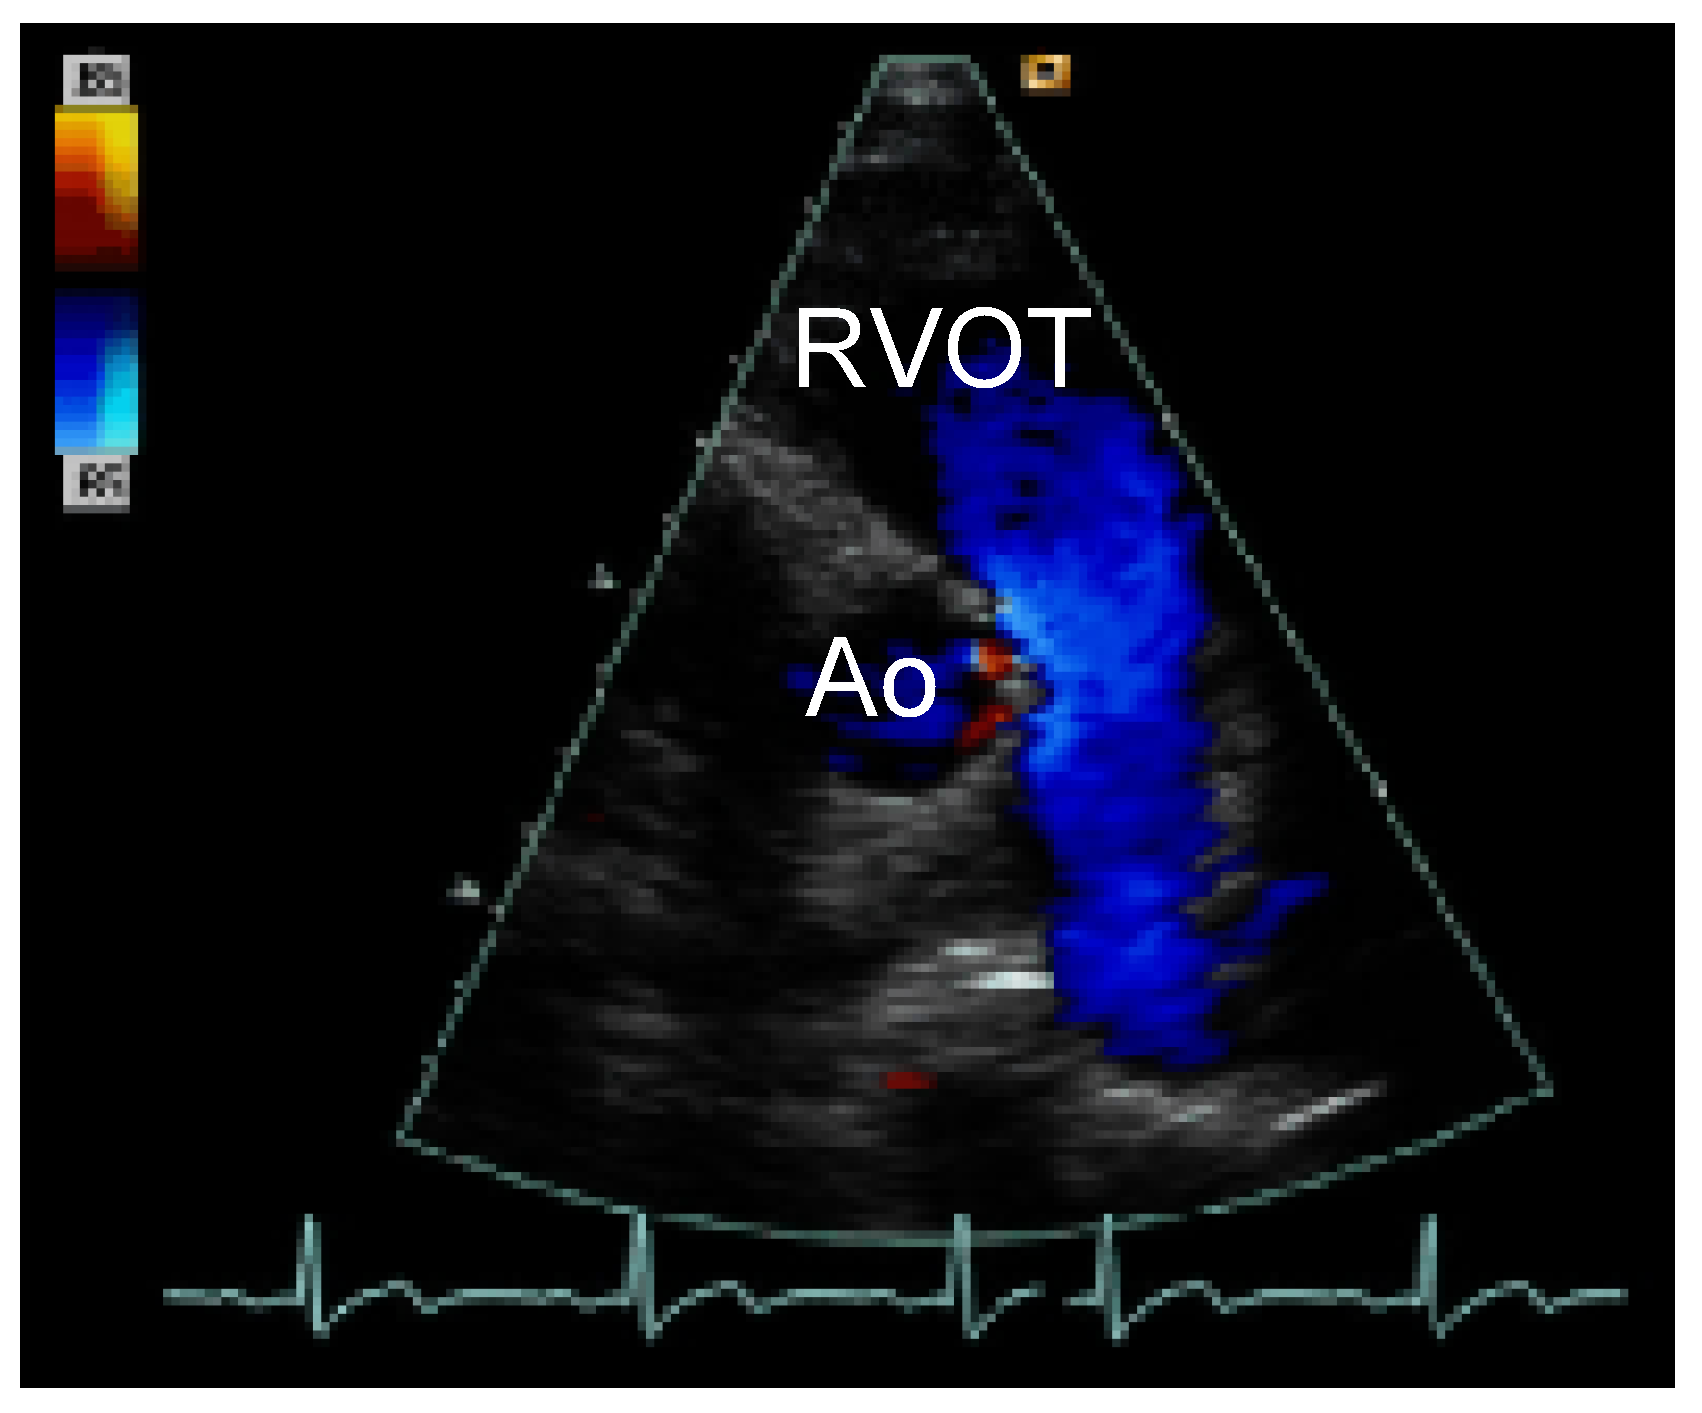

Straight into the Heart: Sinus of Valsalva Injury

Case description